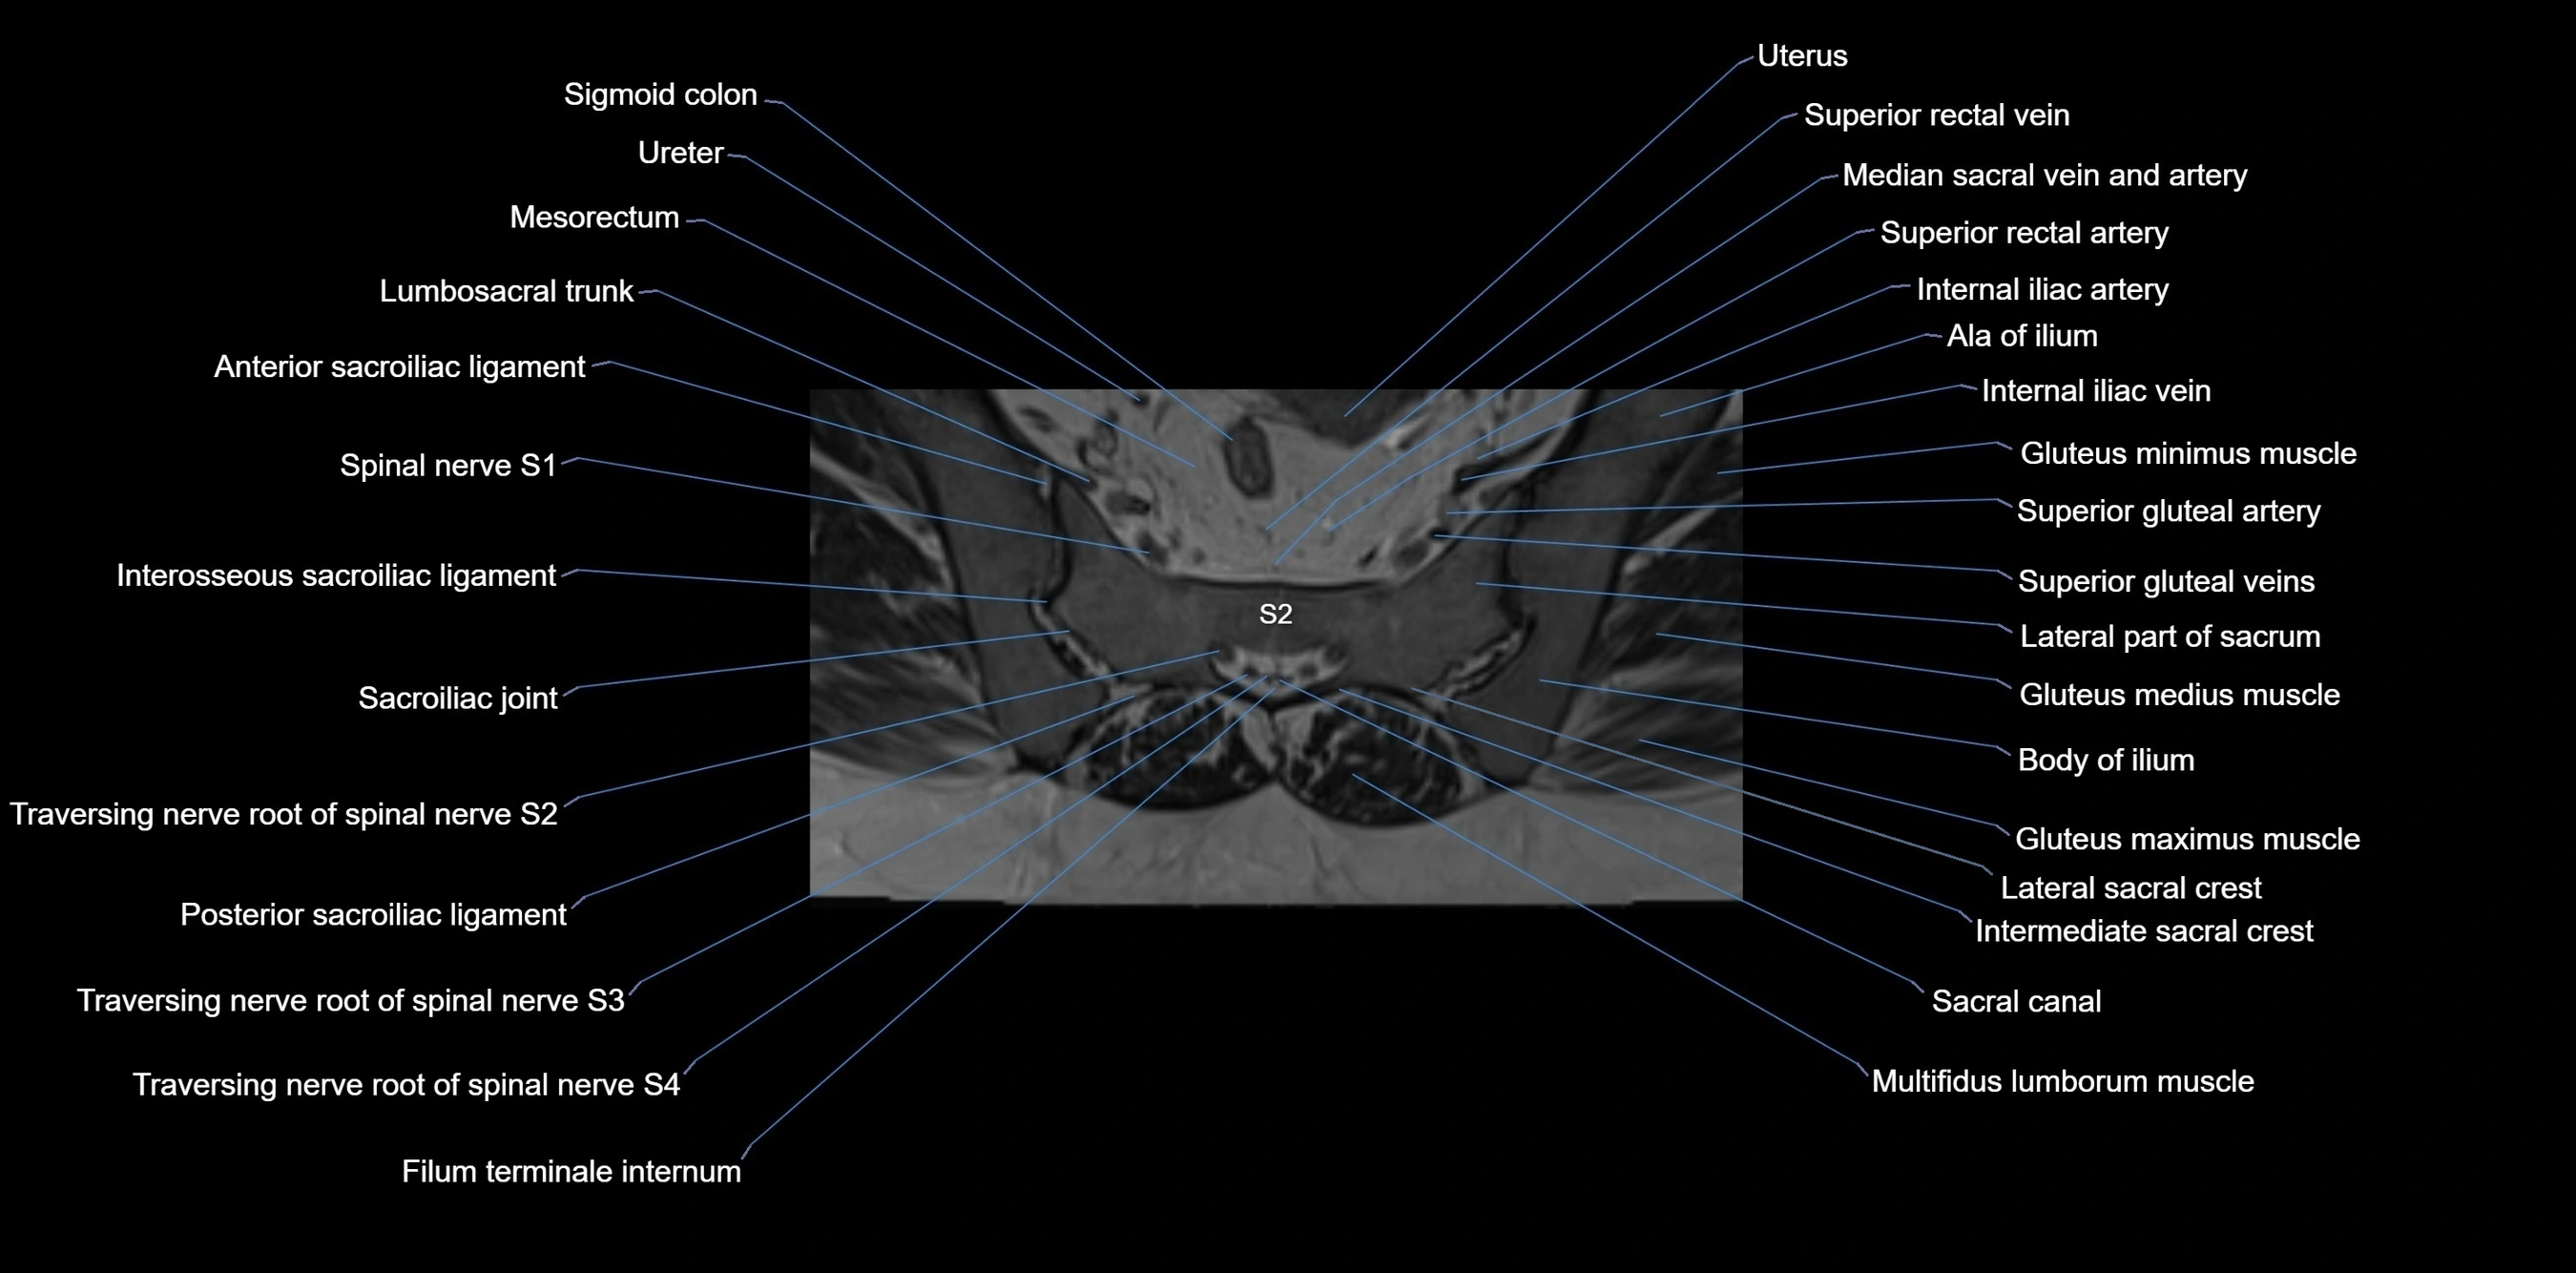

MRI image

image